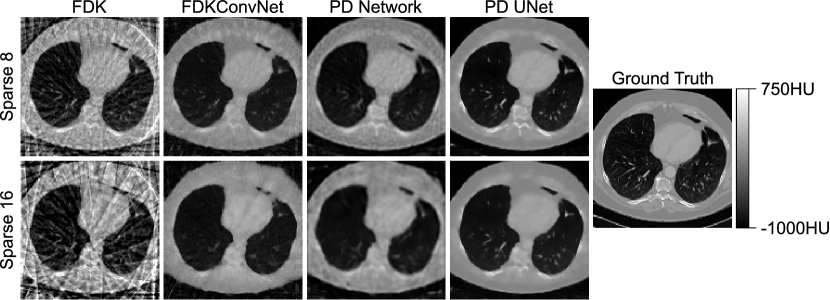

fig:example

fig:example shows an exemplary axial slice from the different models for Sparse 8 (top row) and Sparse 16 (bottom row). FDKConvNet does not seem to have learned anatomical structures and merely attempts to suppress streaking artifacts. Primal-Dual Network produces results that look blurrier with more low frequency noise than FDKConvNet’s outputs but anatomical structures, e.g. costal cartilage, are preserved better. The reconstructions of Primal-Dual UNet are superior compared to Primal-Dual Network. Tissues with high attenuation coefficients are clearly distinguishable from soft tissues and edges are well preserved, e.g. vertebrae, even for the higher sparsity factor Sparse 16.